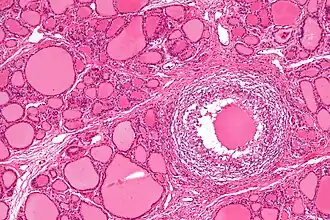

Subacute granulomateuze thyreoïditis of thyreoïditis van De Quervain is een zeldzame vorm van ontsteking van de schildklier.